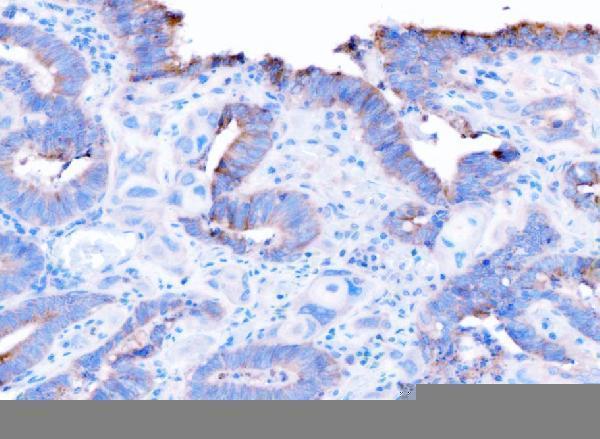

Facts about Disintegrin and metalloproteinase domain-containing protein 9.

Cleaves and releases a number of molecules with Significant roles in tumorigenesis and angiogenesis, such as TEK, KDR, EPHB4, CD40, VCAM1 and CDH5.

| Gene Name: | ADAM9 |